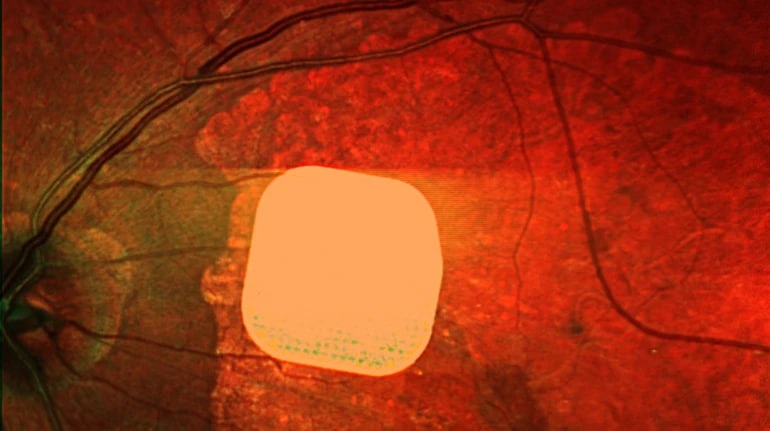

Британські лікарі з клініки Moorfields Eye Hospital разом з колегами з інших європейських медичних закладів успішно випробували новий електронний імплант Prima, який допомагає пацієнтам із макулодистрофією, що призводить до втрати зору у людей після 50 років. Цей мікрочип, встановлений під сітківку ока, сприяє частковому відновленню зору. Під час операції пацієнта під’єднують до системи окулярів доповненої реальності, яка допомагає передавати зображення на мікрочип. Дослідження, в якому взяли участь 38 пацієнтів, показало, що після адаптації більшість з них можуть розрізняти літери, цифри та слова. Лікарі вважають, що ця технологія відкриває нові можливості для людей зі зниженим зором, допомагаючи покращити їхню якість життя та незалежність.

Британські лікарі частково повернули зір пацієнтам за допомогою мікрочипа